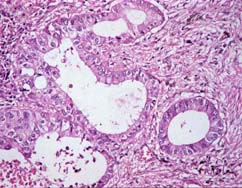

立方型あるいは不整型の癌細胞が管腔形成を示している。